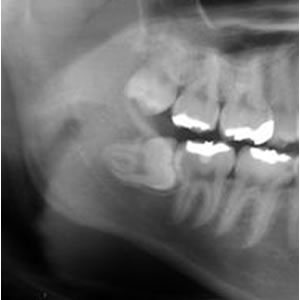

今日行ったところでは、普段どおりに歯の検診、レントゲン撮影(上記の画像は私のではありません)、そして、診断の内容を医師から説明を受ける。

ここの病院の先生は、「ここの親知らずやったら、他の病院ではできんとこがおおいんちゃうか。うちやったら15分くらいあれば簡単に抜ける。」